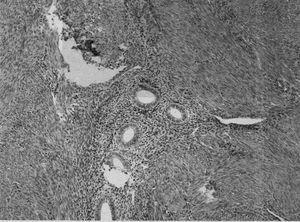

El diagnóstico definitivo se lleva a cabo en el estudio histológico de las piezas de histerectomía (fig. 1), aunque se está realizando una tentativa seria de diagnóstico preoperatorio mediante las biopsias miometriales y el diagnóstico por la imagen (ecografía transvaginal y resonancia magnética). A pesar de que la adenomiosis se presenta en el 5-70% de las pacientes y que se asocia hasta en un 80% de los casos con miomas, los informes de ultrasonografía raramente informan de adenomiosis. En este sentido, el rol de las imágenes en la evaluación de estas pacientes permitirá establecer una aproximación diagnóstica, determinar la profundidad y la extensión de la penetración del miometrio y monitorizar la evolución de las pacientes que reciban terapia conservadora.

Fig. 1. Adenomiosis. Componente glandular endometrial en el seno de miometrio normal.